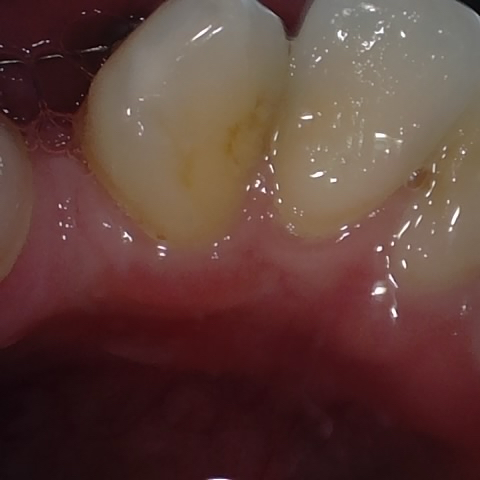

Image 317 / 400

NHD20794

Annotated as "Good"

Original Image Rendering Image